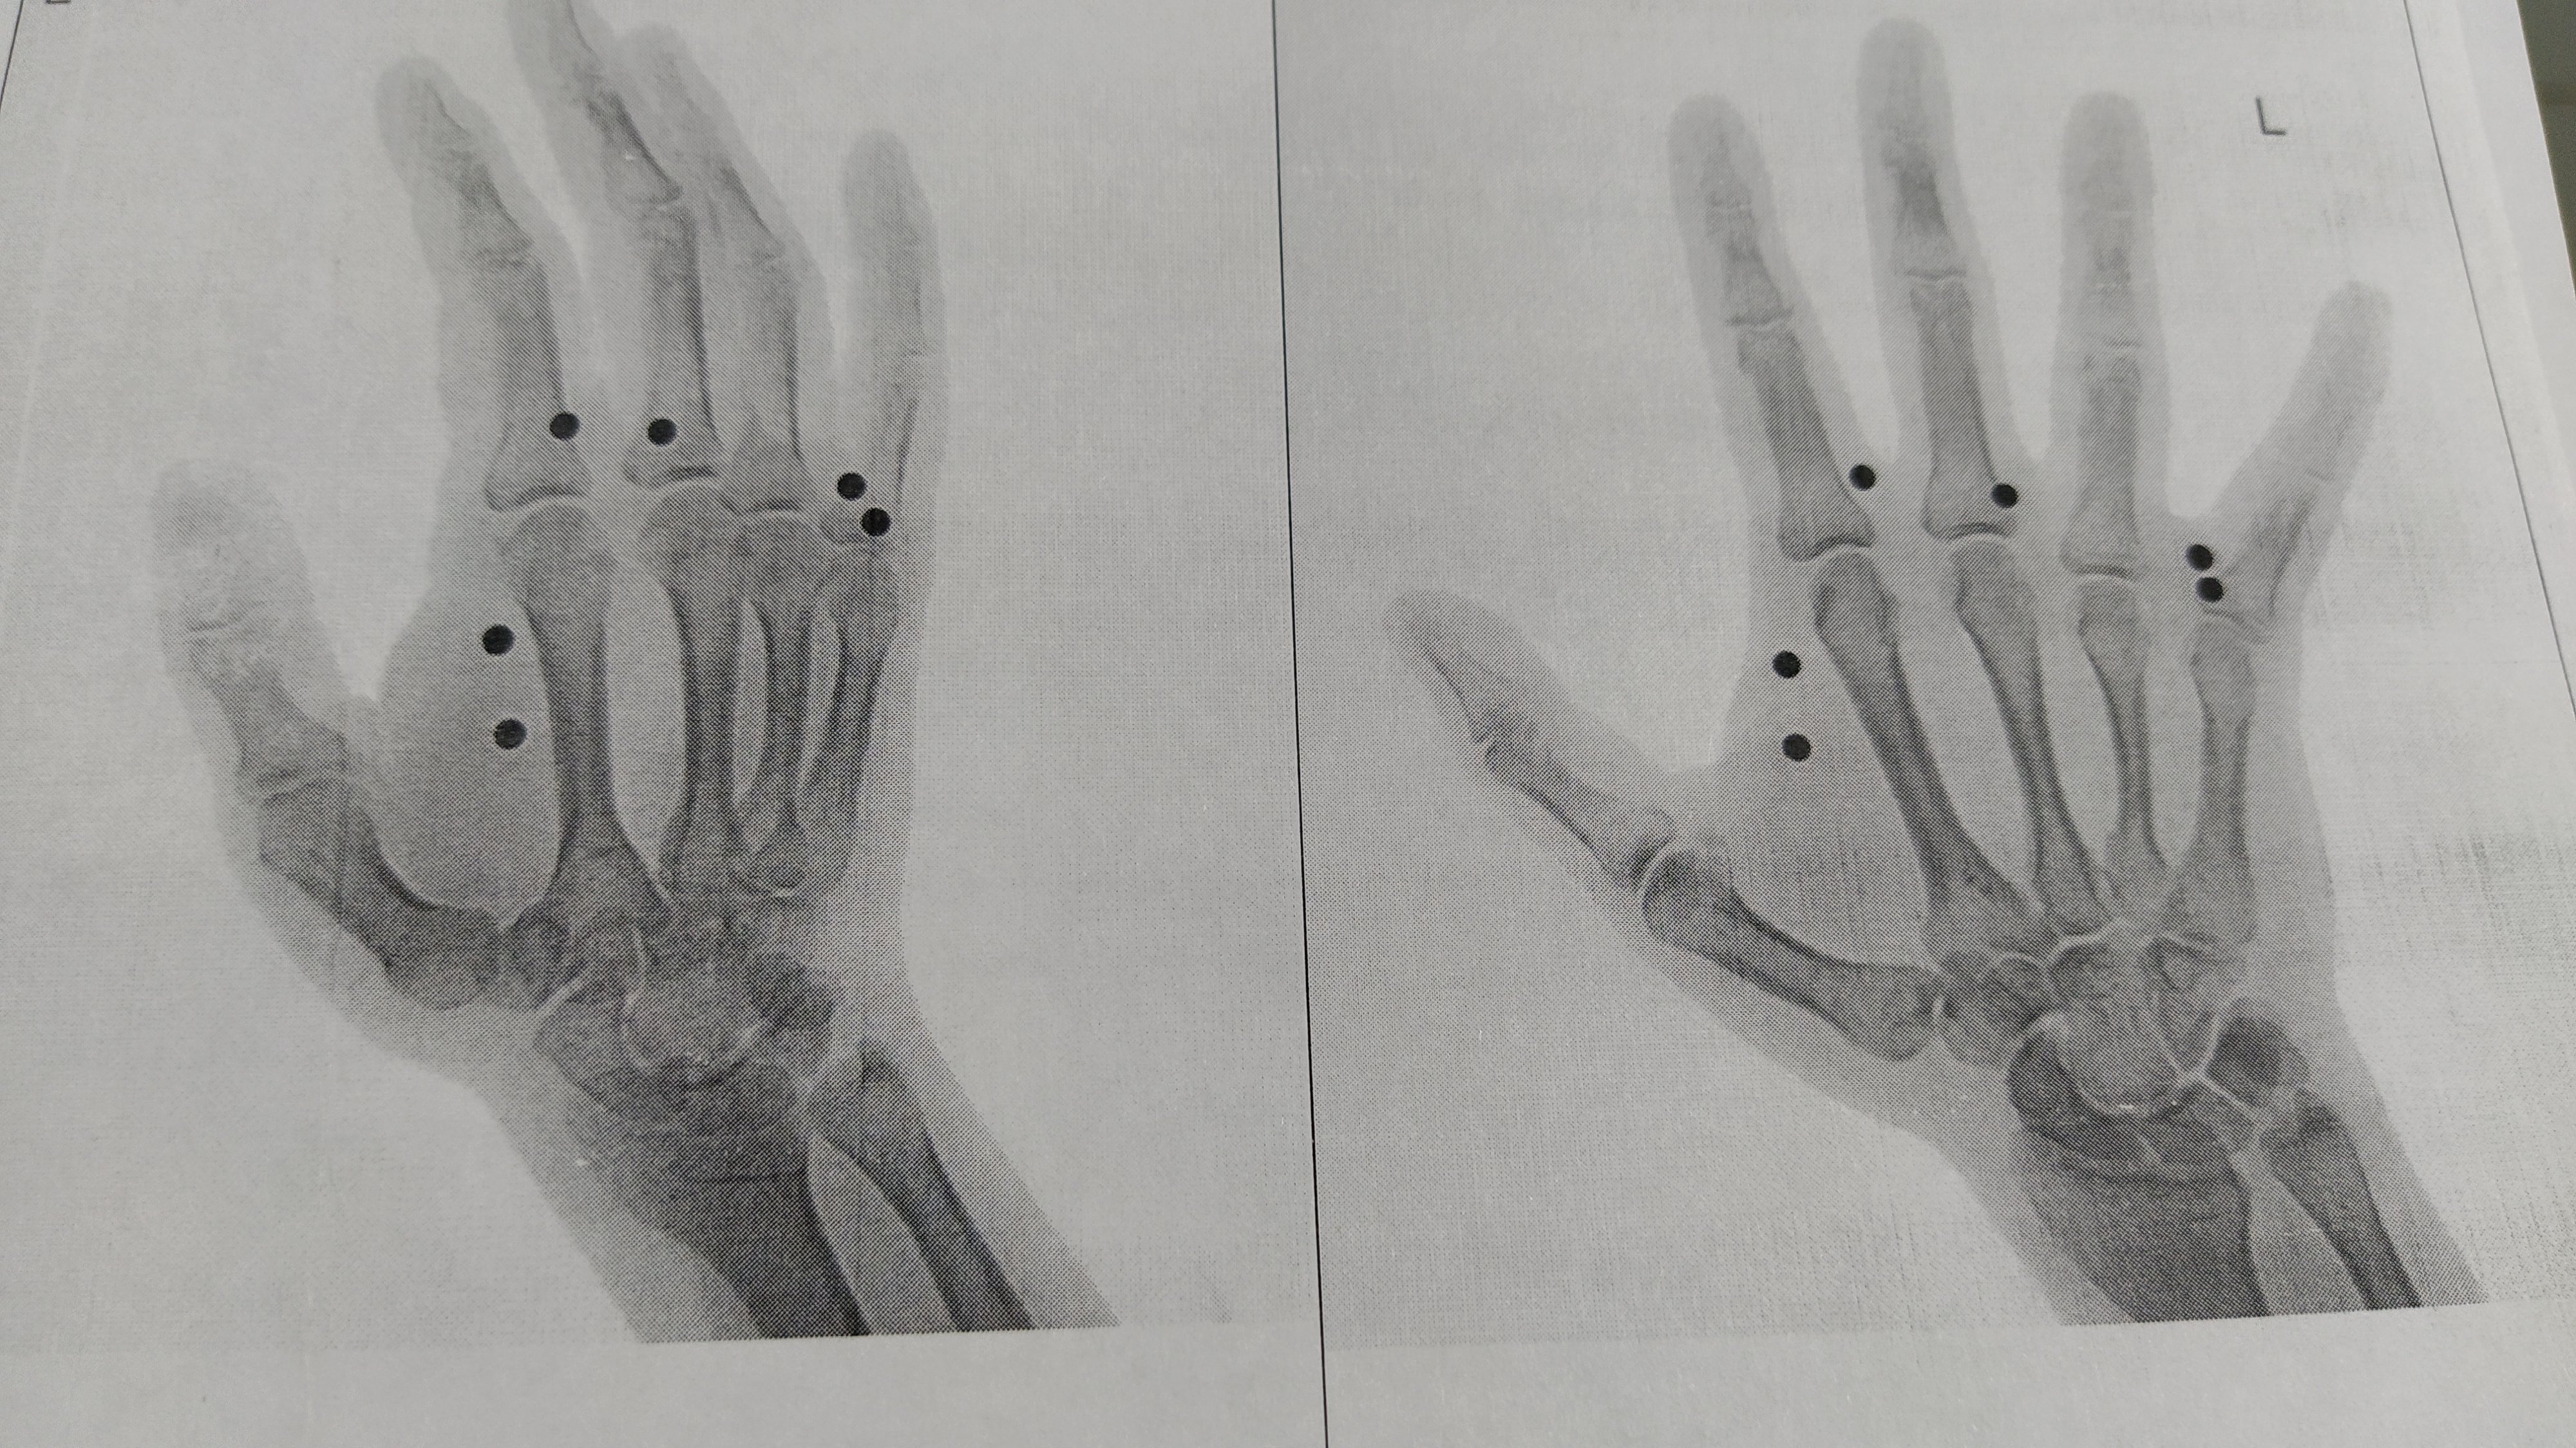

Привет, анон. Я ебанутый, плюсом осень. В общем, я посмотрел как живут мои бывшие друзья, одноклассники, одногрупники, стало очень грустно. Я не знал как побороть грусть, не знал как с этим справится и прибег к единственно известному мне варианту - я расстрелял себе руку из пневматического пистолета. 13 пуль, 7 навылет, 6 осталось в руке.

Решил поехать в травму через сутки, так как рука опухла и один из шариков засел в кости.

>>257255335 (OP) > 13 пуль, 7 навылет, 6 осталось в руке. > 3 Где 13 дырок? Видно только те отверстия, что и на рентгене, должно быть еще 7 дырок от пуль, которые прошли навылет. Кого ты пытаешься наебать?